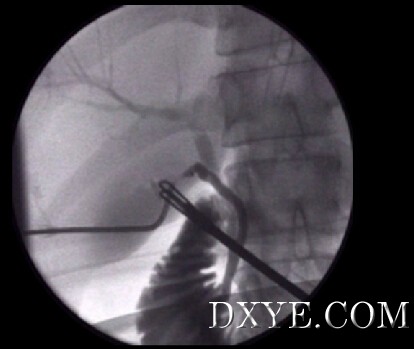

• 3个步骤

登录/注册后可看大图

胆道造影应该在3个步骤中完成:

1. 在射线照相指导下,将几毫升稀释的对比剂注射到胆管中。 静态胆管造影能够检测CBD石块。

2. 继续染料注射,直到获得完整的胆管造影。执行第二张放射线照片以确认。这个体位可以促进肝内胆管造影。

3. The passage of dye into the duodenum under low pressure should be confirmed by a third radiograph.

• 结果

X线显示怀疑在胆总管结石的存在:

- 射线可透性缺陷;

- 一种新月形堵塞的对比;

- 胆管扩张;

- 十二指肠的对比的缺失.

决定进行胆管探查或胆总管将基于对结石及胆管的形态定位分析。